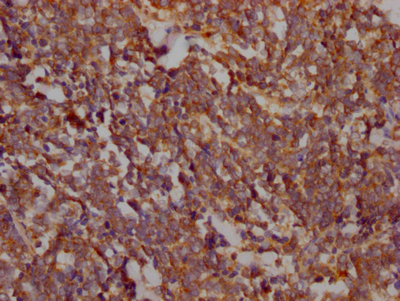

IHC image of CSB-RA198162A0HU diluted at 1:100 and staining in paraffin-embedded human lung cancer performed on a Leica BondTM system. After dewaxing and hydration, antigen retrieval was mediated by high pressure in a citrate buffer (pH 6.0). Section was blocked with 10% normal goat serum 30min at RT. Then primary antibody (1% BSA) was incubated at 4℃ overnight. The primary is detected by a Goat anti-rabbit IgG polymer labeled by HRP and visualized using 0.05% DAB.